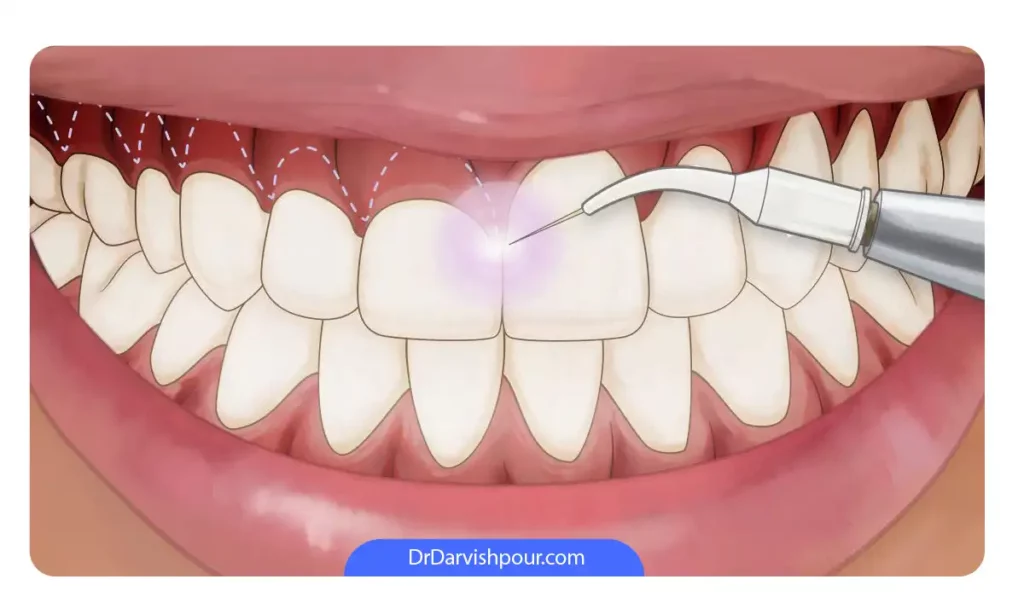

5. لیزر درمانی (Laser gum contouring)

با استفاده از لیزرهای مخصوص دندانپزشکی، دندانپزشک می تواند به از بین بردن بافت اضافی لثه کمک کند. مزیت لیزر در این است که دیگر نیازی به استفاده از تیغ جراحی برای برش و سپس بخیه بافت لثه نیست. لیزر در واقع روشی سریع و کم تهاجم برای اصلاح لبخند لثه ای است.